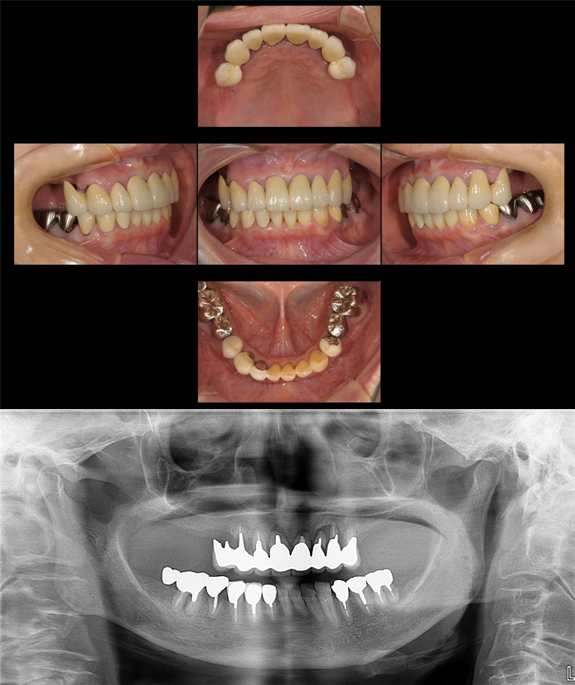

症例2

術前

「食事を美味しくしたい。」ということで来院されました。お口の中はほとんど前歯の噛み合わせしかありません。義歯は作ったけれど合わずに全く使ってないそうです。

術後

インプラントでしっかりとした奥歯を作ることで、なんでも美味しく食べることができるようになりました。